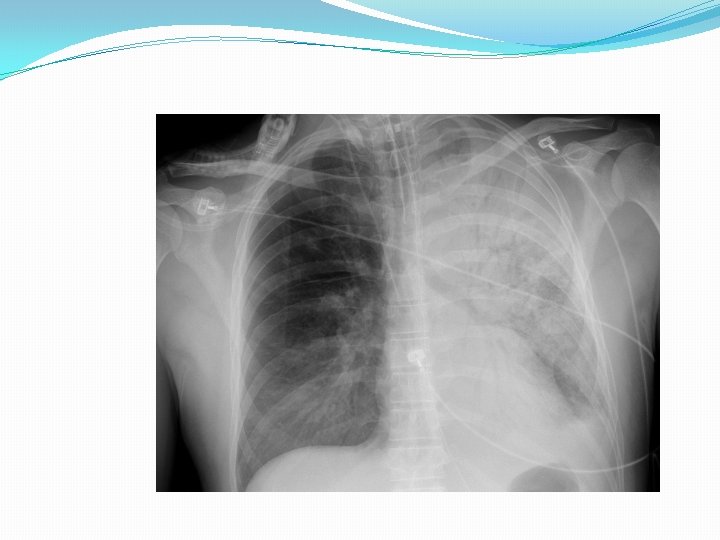

Pneumonia �Pneumonia is defined as infection of the lung parenchyma (that is of the alveoli rather than the bronchi or bronchioles) and characterized by consolidation. (Consolidation is a pathological process in which the alveoli are filled with a mixture of inflammatory exudate, bacteria and WBCs that on chest X-ray appear as an opaque shadow in the normally clear lungs)

Diagnosis �Diagnosis of pneumonia in many cases is made based on the presence of clinical signs and symptoms. �Chest x-ray are often used to confirm the diagnosis.